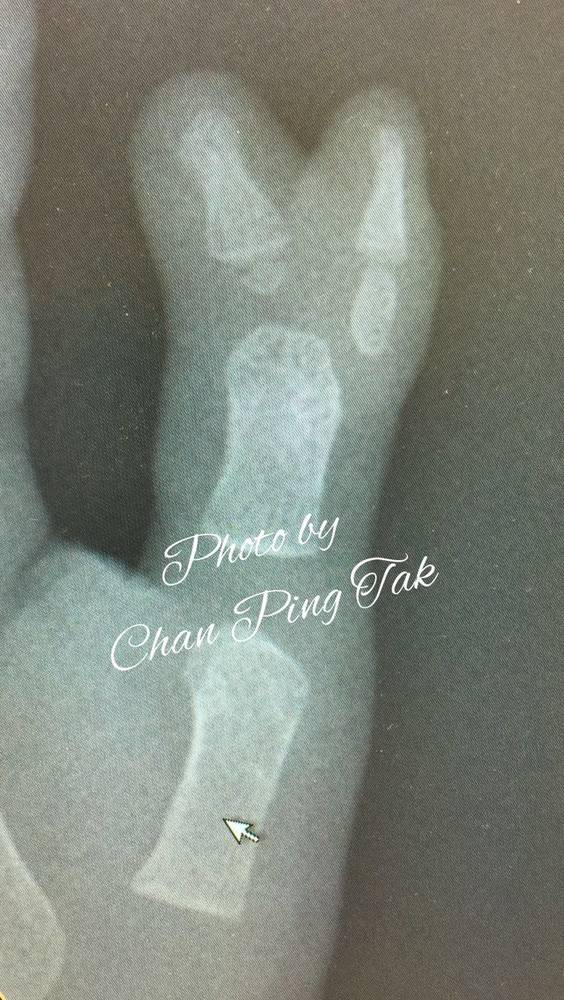

香港屯门医院陈平德教授的作品

一例桡侧多指

是一节还是两节?

切除术后做了病理切片

显示多指为一节

骨骺肥大